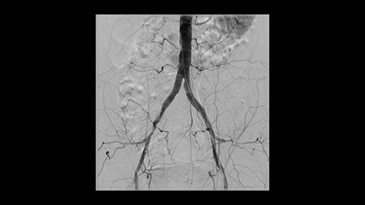

-

İliyak stentlemesi